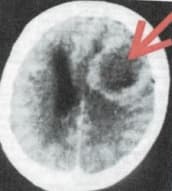

Головний мозок: СДХ в мозочку – там, де знаходиться центр управління молочними залозами – з’являється так званий Осередок Хамера у вигляді концентричних кілець, які можна побачити на знімках КТ мозку.

Рентгенівська комп’ютерна томограма (КТ) дає можливість пошарового дослідження мозку. Саме на КТ знімках (МРТ-знімки не підходять) видно Осередки Хамера (ОХ, кругові структури), місце виникнення яких точно показує, які органі тіла вражені конфліктом. Крім того, за станом ОХ можна визначити, чи знаходиться конфлікт в активній фазі (ОХ видно як чітко окреслені концентричні кола), або пацієнт вже перебуває на шляху до одужання (межі ОХ розмиті внаслідок накопичення рідини, що викликає його набряк).

Після повного відновлення на КТ-знімках на місці колишнього ОХ видно лише зовнішній контур (див. фото справа), як свідчення того, що ДБС повністю завершила свою роботу. На фізіологічному рівні тут залишається «рубець» із сполучної мозкової тканини (глії). Саме на етапі оздоровчого набряку, якщо в цей час зробити знімок мозку (див. фото справа), або після завершення процесу відновлення мозку (іноді – через багато років!), людині ставлять діагноз «пухлина мозку» та спрямовують на зовсім непотрібну (а часто і просто небезпечну) операцію. Осередки Хамера – це «дактилоскопія душі». Вони – живі докази того, що через мозок психіка керує всіма органами тіла!